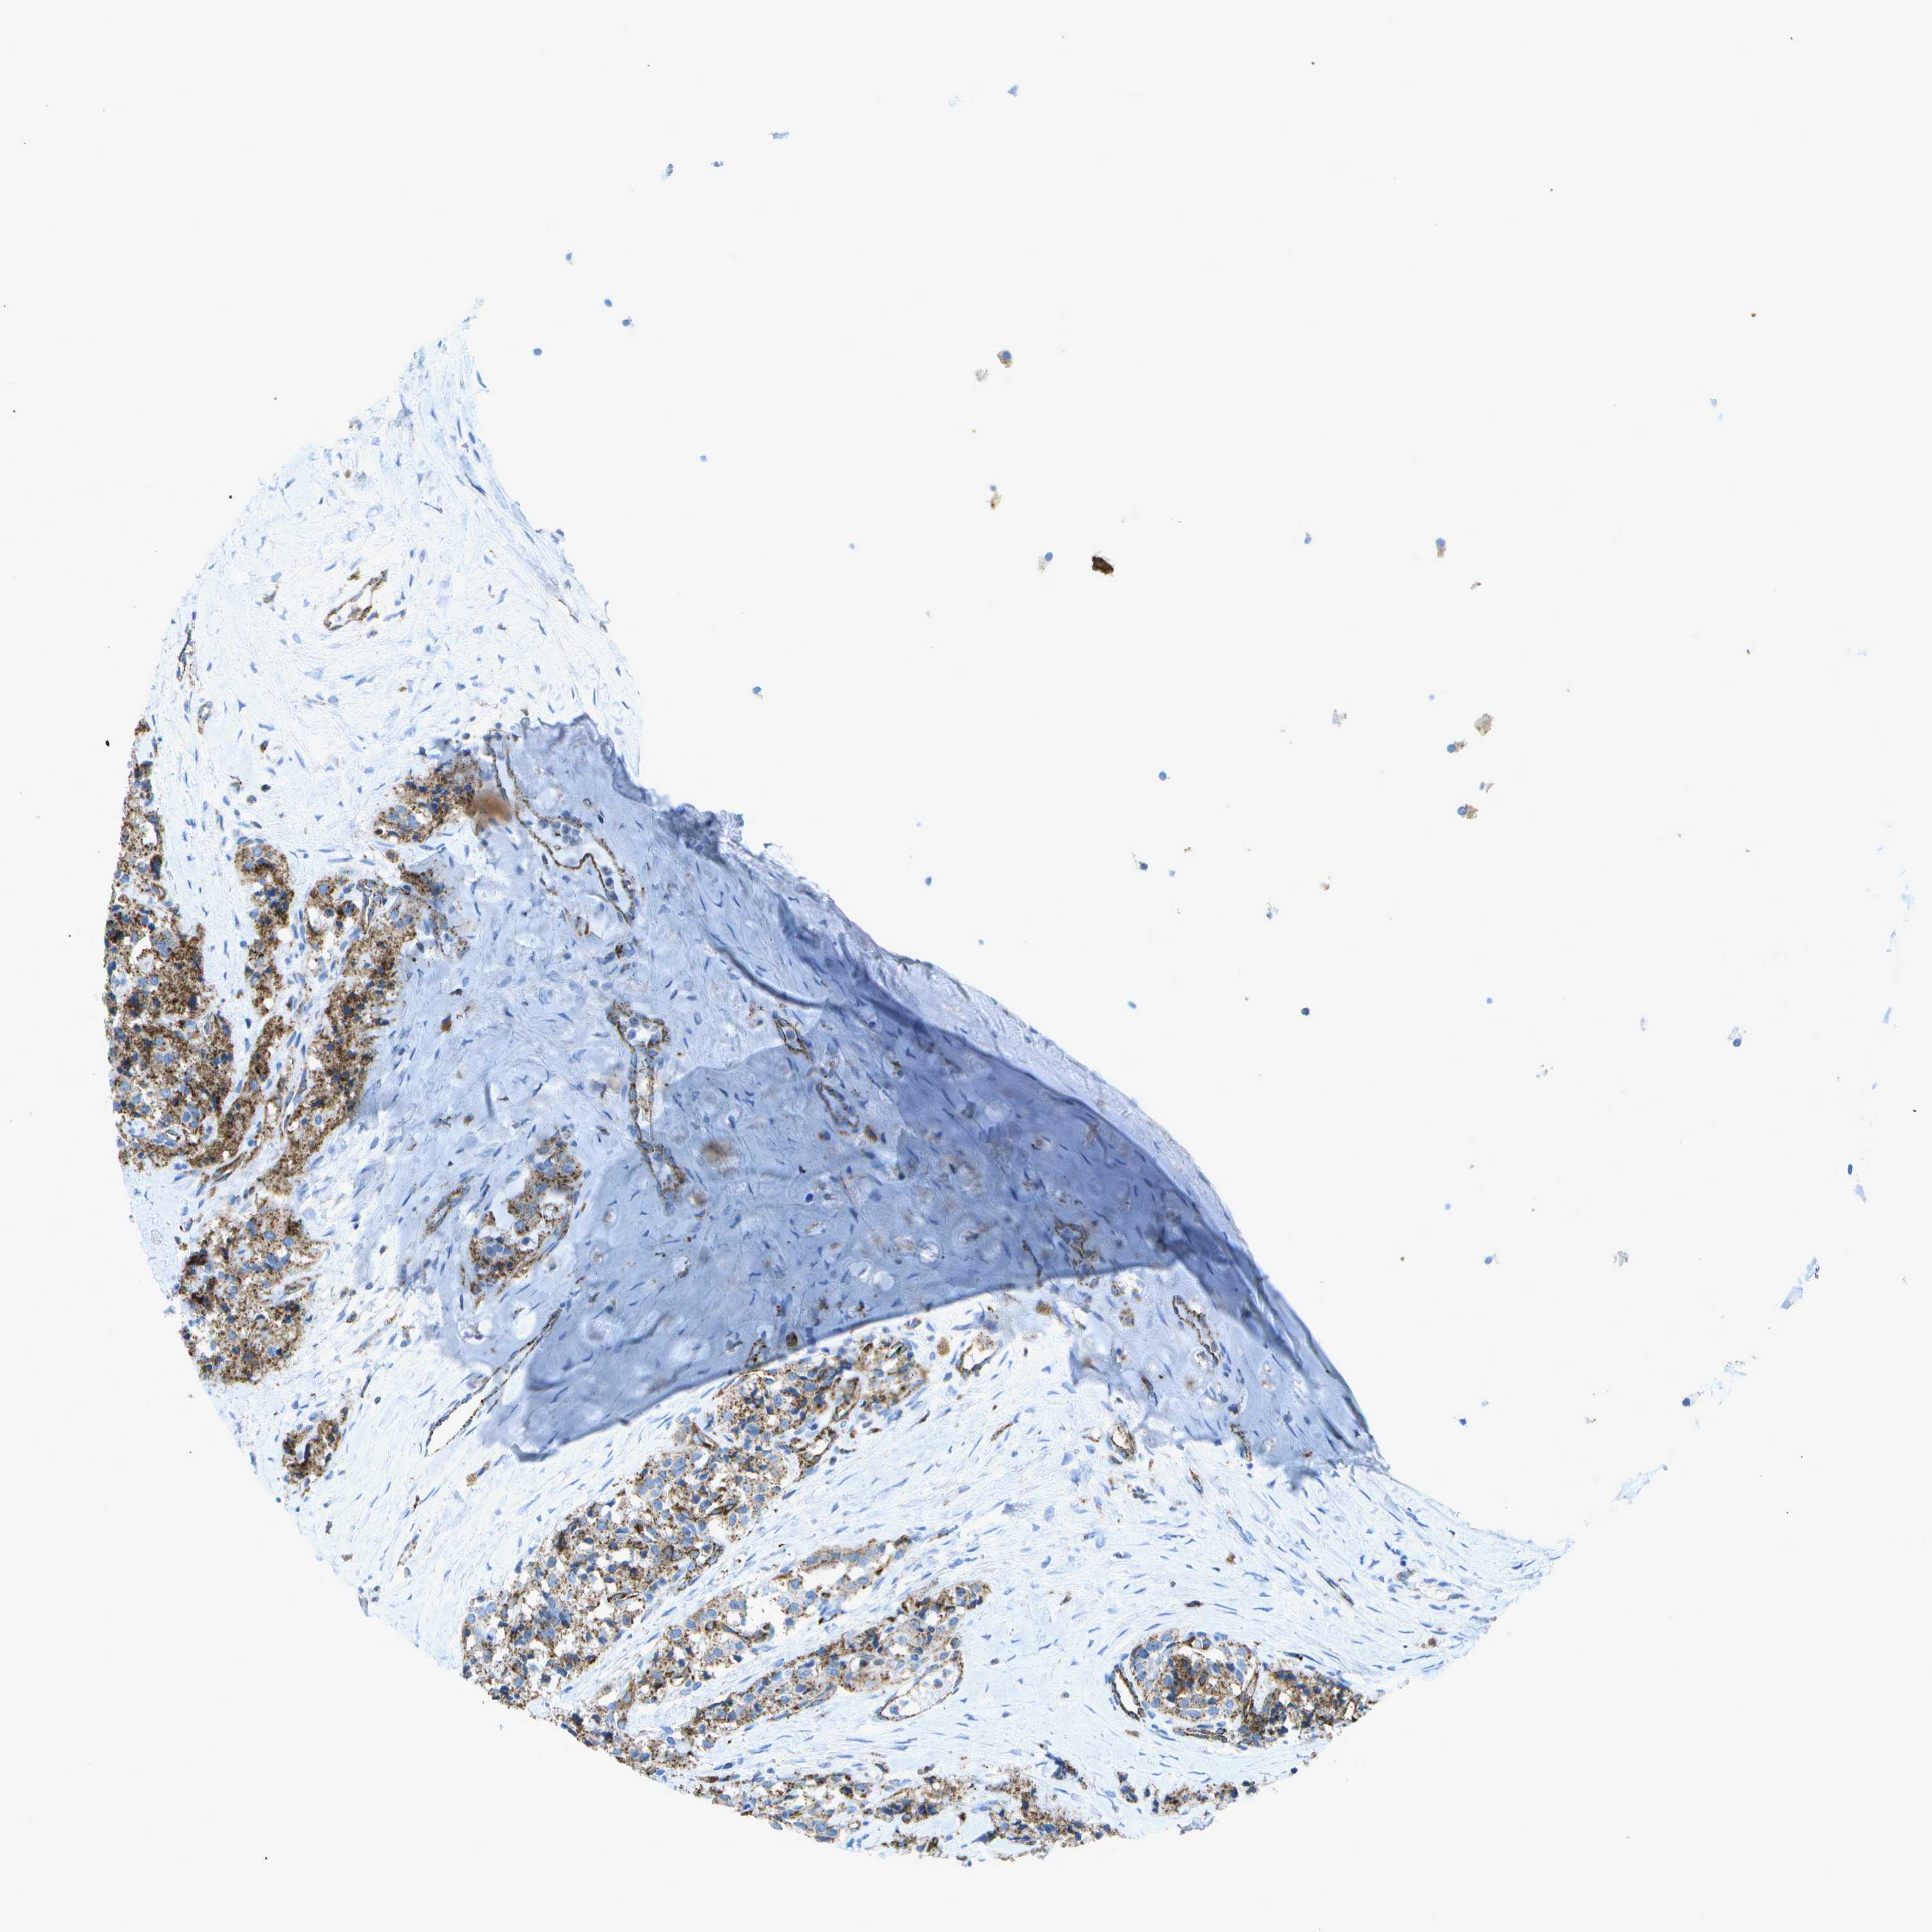

CARCINOID - Protein expressioni

A mouse-over function shows sample information and annotation data. Click on an image to view it in a full screen mode. Samples can be filtered based on level of antibody staining by selecting one or several of the following categories: high, medium, low and not detected. The assay and annotation is described here.

Each image is clickable and will lead to virtual microscopy that enables deeper exploration of all samples and also displays staining intensity scores, fraction scores and subcellular localization as well as patient and tissue information for each sample.

Antibody HPA017065

Staining

High

Medium

Low

Not detected

Intensity

Strong

Moderate

Weak

Negative

Quantity

>75%

75%-25%

<25%

None

Location

Nuclear

Cytoplasmic/membranous

Cytoplasmic/membranous,nuclear

Carcinoid, malignant, NOS